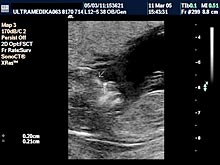

B) Drugi marker je registrovanje postojanje povećane debljine prozračne zone (NT) u vratu ploda-embriona. Obično greške nastaju kada se kontura vrata ploda ne razlikuje od amniona - opne u kojoj se plod nalazi. Osim znanja doktora, rezolucija slike Ultrazvučnog aparata čini ključnu ulogu u merenju ove strukture. Ona-NT se meri u periodu od 9 do 14 GN. Iako je najveća normalna debljina NT 2,5 mm na kraju 14 GN ova vrednost NT može ukazivati na trizomiju ako je registrovana na početku ovog vremenskog perioda. Samo Ultrazvučna kompjuterizovana tomografija može u velikom procentu pouzdano izmeriti ovu strukturu i to na dva načina. Pregled endovaginalnom sondom Braund-band od 8-4MHz, često zbog pozicije ploda nije u stanje da adekvatno registruje NT. Pregled se može znatno zbog toga produžiti i ne mora tačno izmeriti debljinu NT. Međutim u ovakvim situacijama upotrebom Braund-band sondi koje koriste ceo opseg ultrazvučnih talasa od 12 do 5 MHz, pregled se u velikom broju slučajeva završava pregledom preko prednjeg trbušnog zida. Ovaj transabdominalni pregled ima prednosti zbog mogućnosti boljeg pozicioniranja ultrazvučne sonde

E) Peti UZ marker u ovoj starosti trudnoće je postojanje nosnih kostiju. Početak njihovog razvoja i veličina zaostaju kod plodova sa trizomijom 21 para. U zadnjih nekoliko godina početno oduševljenje lekara da je ovo ključni marker u otkrivanju hromozomskih anomalija je splasnuo jer je nekoliko velikih studija otkrilo da on nije tako senzitivan. Međutim nova otkrića su ponovo povećala značaj ovog markera. Prvobitni način merenja nosnih kostiju je bio pogrešan. Naime, tek naknadno je shvaćeno da su čeone kosti tek počele svoj razvoj i da su znatno udaljene jedna od druge u ovoj starosti ploda, te na tačnom sagitalnom prikazu ploda ove se čeone kosti ne mogu uočiti. Tek na ovakvom ultrazvučnom preseku možemo procenjivati prisustvo i veličinu nosnih kostiju. Ako su na profilnom snimku bebe prisutne frontalne kost onda se na mestu nosnih kostiju vidi nastavak gornje vilice a ne nosne kosti. Bez Broand band endovaginalnih sondi i transabdominalnih od 5-12 MHz nema govora o proceni ovog markera. Takođe se na ovom preseku meri i veličina gornje vilice i uva ploda što skupa povećava znatno osetljivost savremene kompjuterizovane ultrazvučne dijagnostike.